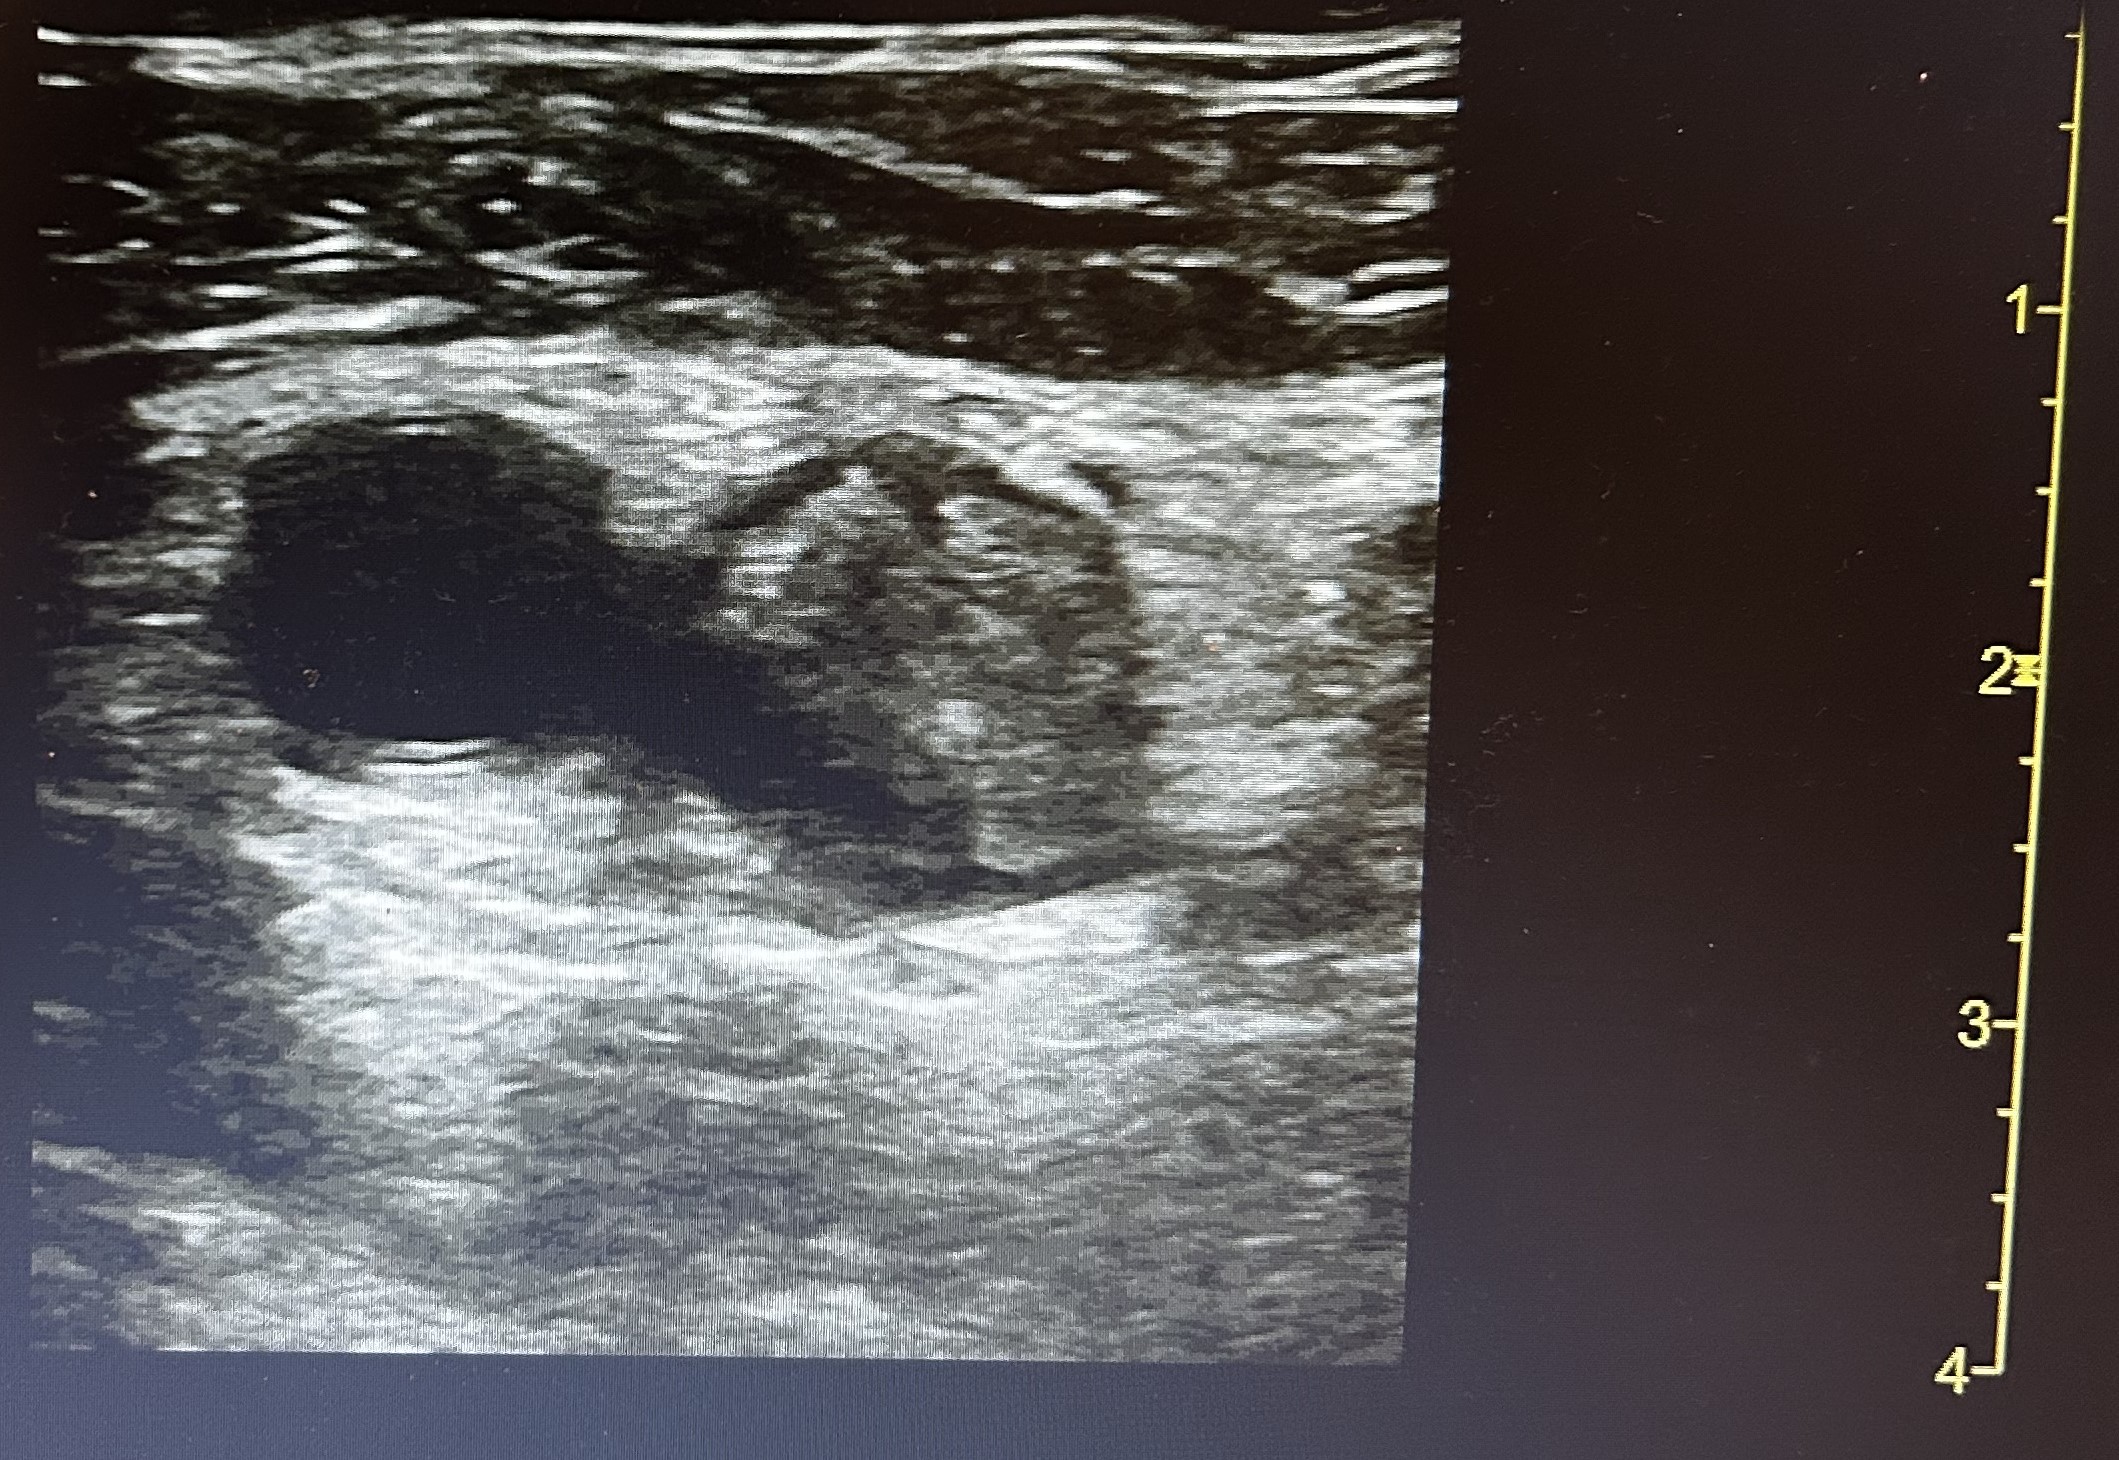

Hallazgos ecográficos

Ante cuadro sugerente de trombosis venosa se realiza ecografía-doppler venoso de la extremidad afectada objetivándose extensa Trombosis venosa profunda con afectación desde vena iliaca externa hasta territorio infrapoplíteo.